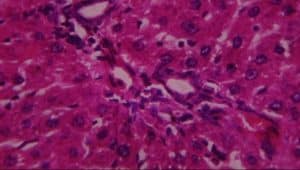

Figure 16: Rat given 400mg extract + lead acetate showing A-periportal infiltrates of inflammatory cells, B-vascular congestion, and C-patchy hepatocyte necrosis (H&E x 400)

On the contrary, evaluating the protective properties of aqueous extract of L. inermis by giving 400mg/kg of aqueous extract of L. inermis and thereafter inducing the injurious effect of 100mg/kg of lead acetate after 30 minutes was disastrous. This is to prove the fact that aqueous extract of L. inermis is useful in the treatment of already damaged liver cells rather than preventing. Clinically, this property of L.inermis could be taken into consideration in humans with similar liver lesions as confirmed histologically in this study: evidence-based anatomy.